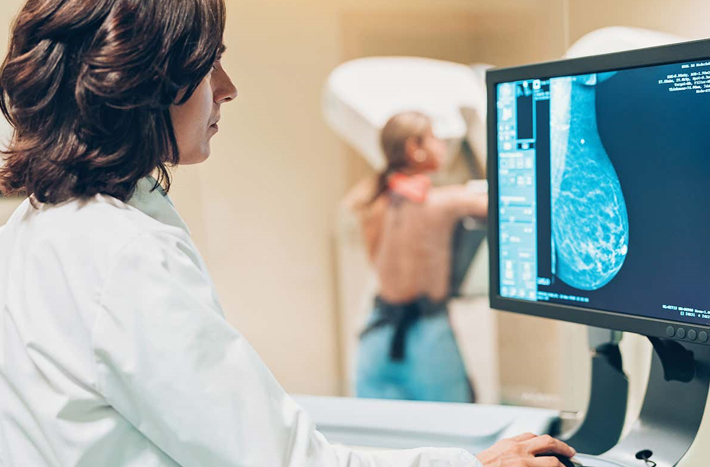

스웨덴에서 유방촬영술 검진을 받는 10만 명이 넘는 여성이 AI 지원 검진 또는 표준 검진에 배정됐다.

표준 검진은 영상의학과 전문의 2명이 각각 영상을 판독하는 방식이었다.

검진은 2021년 4월부터 2022년 12월 사이에 진행됐다.

AI는 어느 날 갑자기 똑똑해진 게 아니었다.

이번 임상시험에 사용된 AI는 10개국이 넘는 여러 국가의 다수 병원에서 수행된 20만 건 이상의 이전 검사 자료로 학습과 검증을 거쳤다고 연구진은 설명했다.